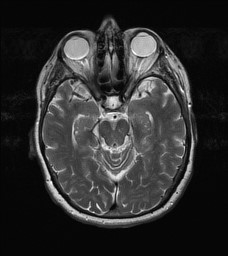

The output of the following code will look like: